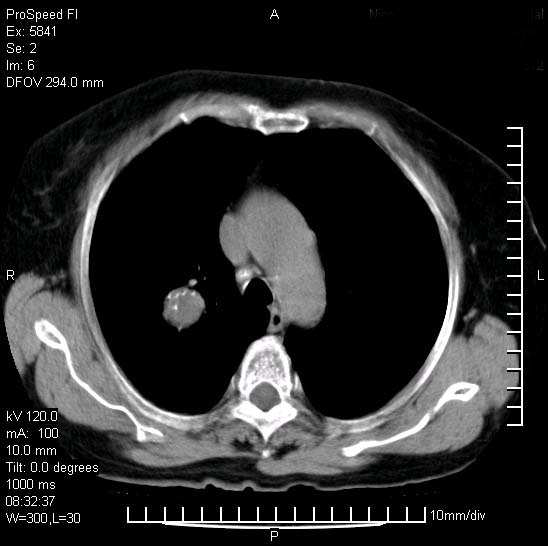

胸痛,咳嗽,气短一周,无发热。右上肺见一结节灶,边缘刺角,内见多个小钙化结节。考虑结核球?肿瘤? 余无异常没有上传。

考虑右肺上叶继发性肺结核,结核球形成。

胸膜是受侵的,考虑感染,结核球可能性大

考虑结核球,并胸膜局限性增厚!!